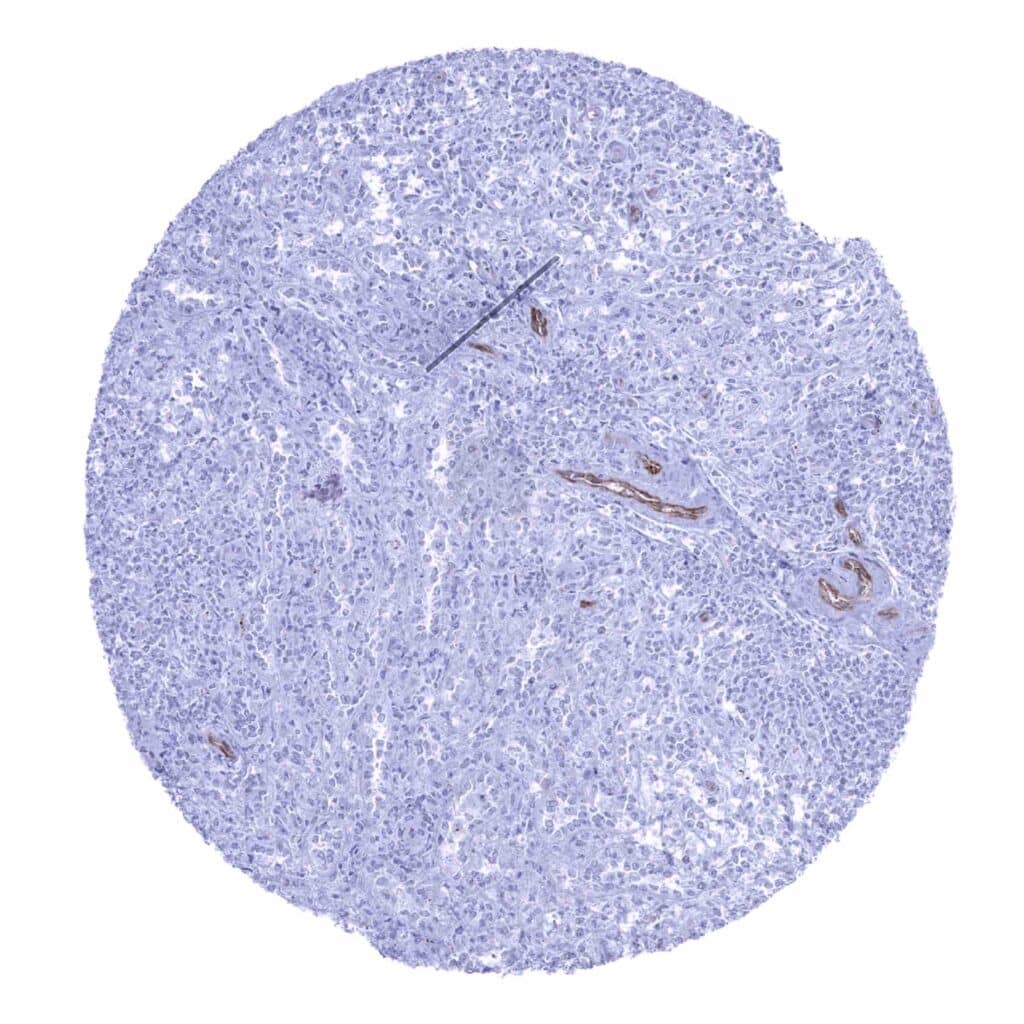

Lymph node – Significant occludin staining of endothelial cells (occludin immunohistochemistry)